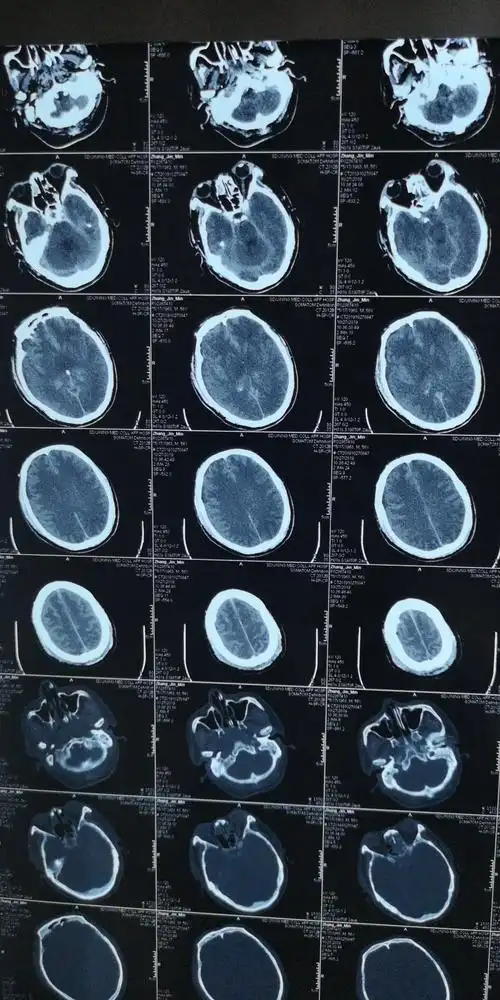

脑疝后ct

左侧海马沟回向内侧移位,基底池模糊,以上提示左侧小脑幕切迹下疝

上行小脑幕切迹疝小脑半球占位导致上行小脑幕切迹疝,小脑半球跨越